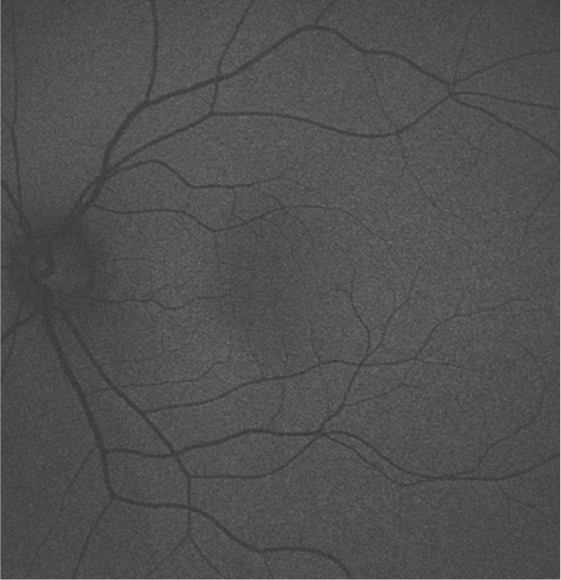

自発蛍光眼底写真

網膜に含まれる自発蛍光物質を撮影し、加齢黄斑変性・網膜萎縮など、網膜組織の機能異常や変化を評価